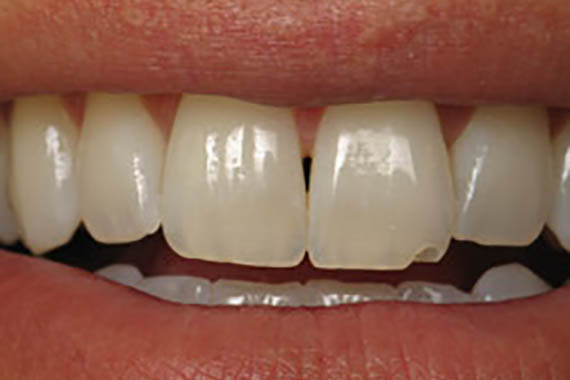

Crowns

Before

After